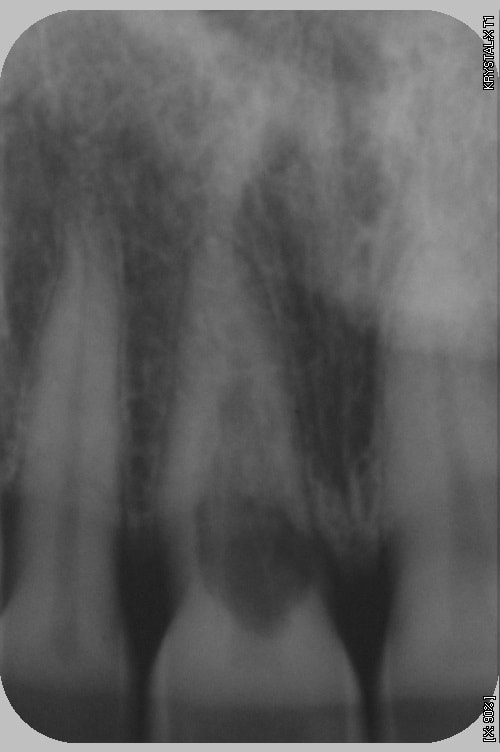

Patiente 39 ans pas d'autres soucis mais le confrère propose l'avulsion...et franchement?

C est carieux ou résorption interne ??

çà c'est une résorption interne....c'est mort....davier et clou....

résorption interne, mais pas trop décidé pour le davier et le clou... patiente limité coté finances

Le problème n'est pas endo mais mécanique. Si la résorption est effectivement interne, ce qui semble être le cas, l'endo stoppera le processus.

Mais après, la perforation semble nettement infra osseuse (scan?), donc quid de la reconstruction? Mécaniquement, en terme d'étanchéité, et de profil d'émergence, ça se traite comme une carie. Et une carie dans cette zone, je ne vois que le davier, ou la traction ortho, qui semble improbable au vu de la taille de la racine.

Il s'agit d'une résorption cervicale invasive d'origine externe. Le point d'entrée est au niveau du collet de la dent juste sous la jonction amelo-cementaire. On le sait car on voit encore l'image du canal au milieu de la lésion. Les résorptions externes n'attaquent que les tissus minéralisés (la dentine) mais pas la pre-dentine qui entoure la pulpe d'où l'image du canal. La dent est probablement encore vivante !

Là, vu l'importance de la lésion malheureusement la seule chose à faire est de programmer le remplacement de la dent avant qu'elle ne casse sur un morceau de pain !

Ps je confirme dent vivante.

radio postée à 15H00 aujourd'hui

La patiente vient d'appeler à 18H00

le dent est cassée

fin de la discussion